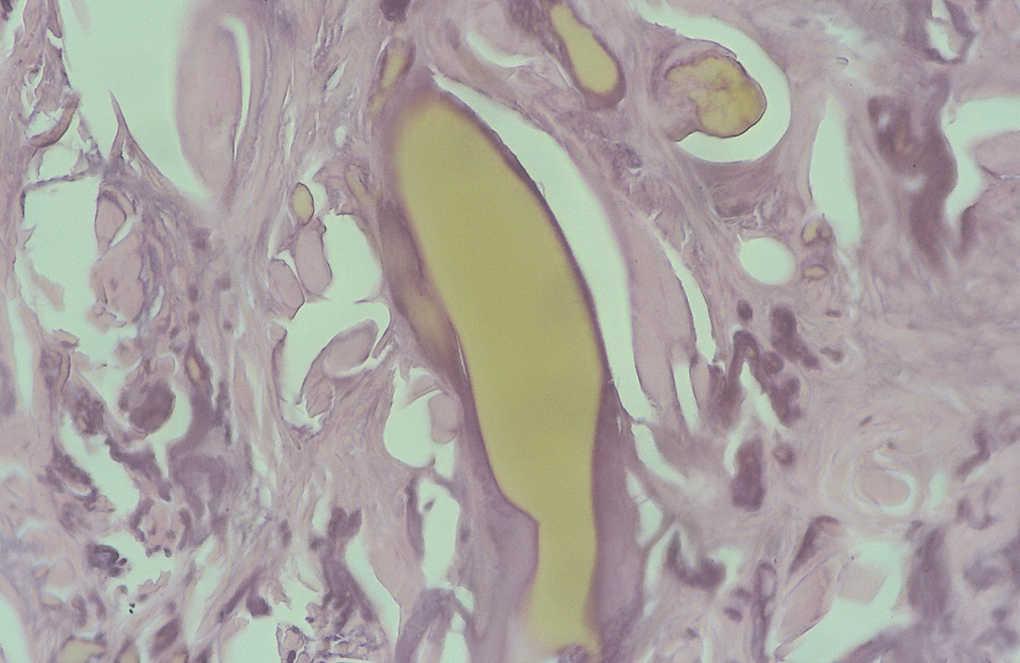

Se tomó, una biopsia de la cara lateral de uno de los índices afectados, y se observó una epidermis discretamente hiperqueratósica y acantósica. En la dermis superficial había una importante elastosis asociada a depósitos de material acelular de color ocre rodeado de una degeneración basófila del colágeno (figs. 3 y 4).

Fig. 4.--Detalle de cúmulos de pigmento de diverso tamaño, el más grande con la forma alargada típica y otras de menor tamaño en íntima relación con las fibras de colágeno de aspecto degenerativo elastótico. (Hematoxilina-eosina, x400.)

En estudios microscópicos de la piel, el pigmento forma depósitos dérmicos, de color pardo-amarillento, redondeados y alargados en forma de plátano y en estrecha relación con masas de colágeno degenerado. En el caso de la biopsia de nuestro paciente se apreciaron claramente los hallazgos más característicos de esta enfermedad: fibras de colágeno irregulares con bordes dentados y fracturadas en relación con cúmulos redondeados y alargados de pigmento amarillento de diversos tamaños. Sin embargo, no se observaron macrófagos cargados de pigmento en el interior de células endoteliales en células secretoras, ni en la membrana basal de glándulas sudoríparas, hecho descrito también en algunos casos de alcaptonuria. Asimismo se apreciaban grandes depósitos en dermis papilar, lo que indica una probable tendencia a la eliminación transepidérmica en nuestro caso, tal y como se ha descrito en casos de ocronosis exógena 7. Sin embargo, en esta última las fibras ocres son de pequeño tamaño, están dispuestas de forma dispersa en toda la dermis y no se describe la presencia de grandes fibras ocres en la dermis superior. Al igual que en la forma endógena, también se aprecian pequeños gránulos de pigmento ocronótico en el interior de macrófagos. En los casos inducidos por hidroquinona los macrófagos cargados de pigmento están situados en la dermis superior y habitualmente asociados a escasa melanina en la capa basal epidérmica. En los casos inducidos por antipalúdicos estos macrófagos se sitúan a nivel perivascular y perianexial 7. La determinación de AHG en orina se considera patognomónica de esta enfermedad (valores normales en orina: < 0,01 mmol de AHG por mol de creatinina o < 10,0 mg en orina de 24 h) 8.